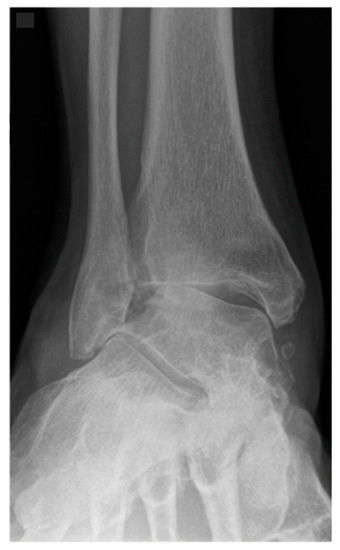

Figure 1.

A 57-year-old male patient presenting end-stage varus tibiotalar osteoarthritis.